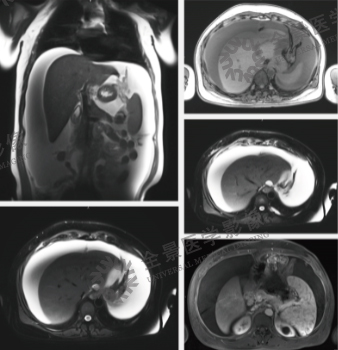

案例:中老年男性,体检发现肝占位,左叶内侧段小结节,约10mm左右,当地普外科考虑小肝癌,建议手术治疗。为明确诊断。我们为他进行MRI普美显增强扫描肝脏大小、形态正常,肝表面光滑,左右叶比例协调,肝裂不宽;肝左叶内侧段见一类隋圆形结节影,长径约10mm,T1WI呈等低信号,T2WI呈等稍高信号,DWI呈稍高信号,增强扫描肝动脉期明显强化,门静脉期及延迟期呈稍高信号,肝胆期呈高信号。

结论:肝脏左叶内侧段结节,诊断:肝脏局灶性结节增生(FNH)。